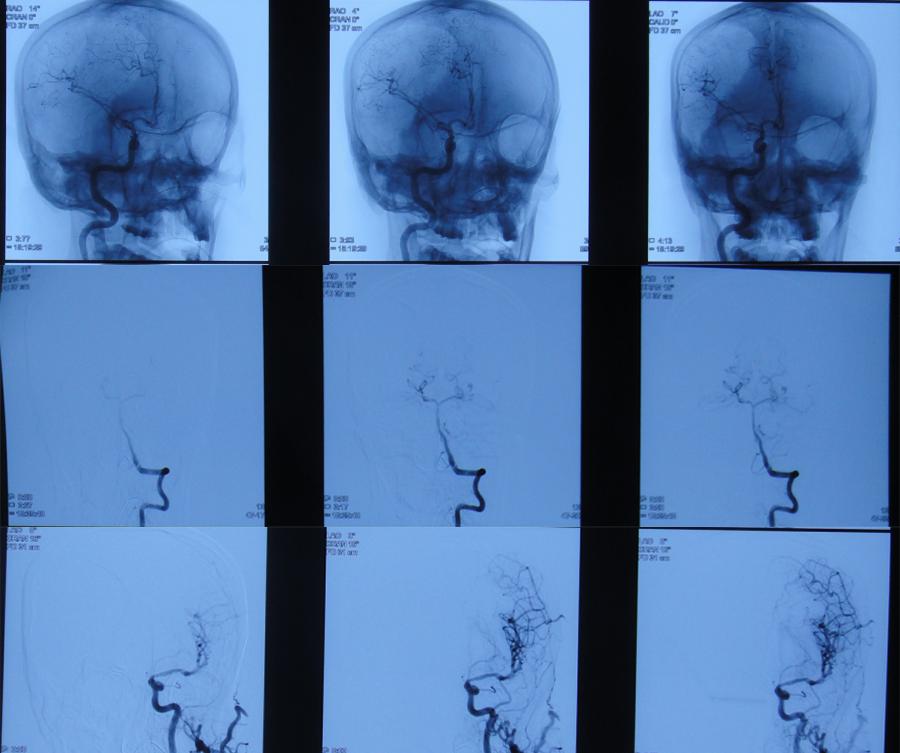

3天后即2019年11月13日,症状未见好转,反而加重,查头颅CTA示“右侧颈内动脉交通段动脉瘤形成”(图-2),当即给予右侧额颞入路颈内动脉瘤夹闭+去骨瓣减压术(片子丢失),术后住入ICU治疗。

图-2:2019年11月13日头颅CTA